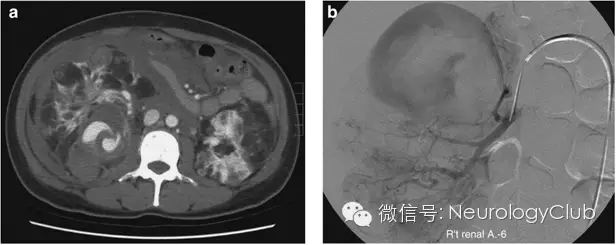

阴阳征表现为增强CT上,在扩张的卵圆形动脉截面内,可见半强化和半无强化区,形态酷似道教的阴阳符号。

阴阳征见于附壁血栓形成的真性和假性动脉瘤患者。动脉瘤为局限性或弥漫性的动脉管腔扩张,大于其正常直径的50%。假性动脉瘤指动脉管壁被撕裂或穿破,血液自此破口流出而被主动脉邻近的组织包裹而形成血肿,多由创伤所致。大动脉瘤和假性动脉瘤容易形成附壁血栓,因此血流仅充盈部分管腔。阴阳征中,造影剂充盈增强的部分代表通畅的管腔,而无造影剂充盈的部分则代表附壁血栓的形成。

病例3:右肾上动脉假性动脉瘤患者